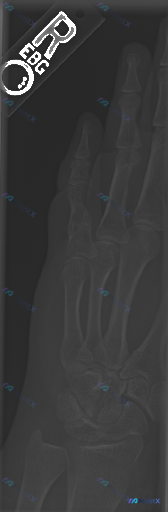

看到一份右手斜位X光片的读片资料,先把影像部分放出来: 影像所见(摘要): - 掌骨、指骨、腕骨形态完整,骨皮质连续,未见明确骨折线、骨膜反应或骨质破坏 - 腕掌、掌指、指间关节对位正常,关节面光滑,间隙未见明显狭窄/增宽 - 骨密度均匀,软组织轮廓正常,未见明显肿胀或高密度异物 影像结论: 在当前...